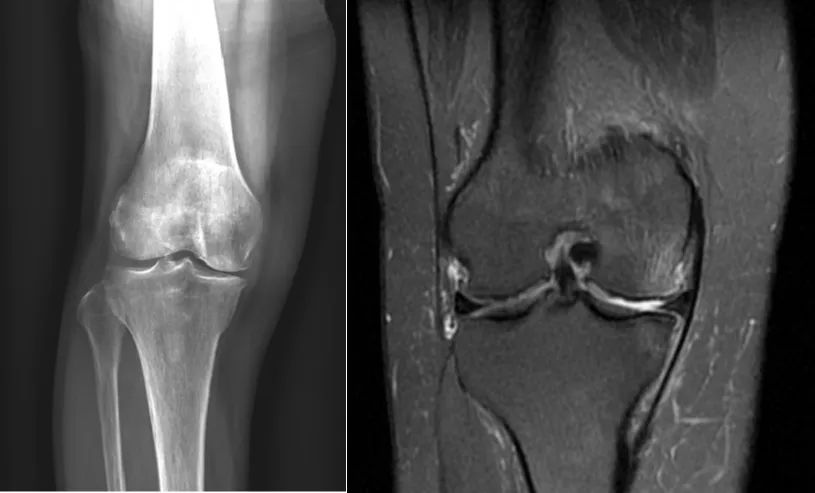

1、前内侧骨关节炎(AMOA),股骨内侧髁或胫骨内侧平台骨坏死

2、前交叉韧带ACL 完好、内侧副韧带MCL 功能完好

3、外侧软骨正常或轻微退

4、内翻畸形 <15°,屈膝畸形 <15°,膝关节可主动屈曲 ≥90°